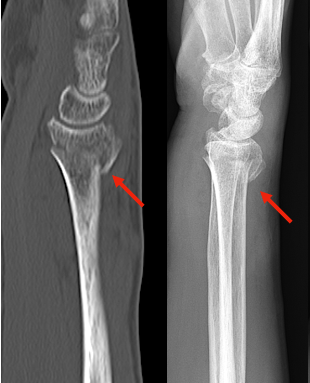

橈骨遠位端(とうこつえんいたん)骨折

✓​橈骨遠位端(とうこつえんいたん)骨折とは?

橈骨遠位端骨折は高齢者受傷しやすい手首の骨折です。転んで手をつくことが原因で起こります。若年から青壮年の方にもみられる怪我のひとつです。怪我の直後から手首周辺の腫れと痛み、場合によってはフォーク状の変形を伴います。さらに時間がたつと皮下出血や指のしびれなどが認められることもあります

骨折の転位によるフォーク状変形

術前CT(矢印が転位した骨片)